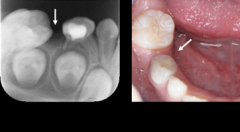

乳牙提前脫落了怎麼辦?

○ 乳牙提前脫落了怎麼辦?

兒童間隙保持的意義 乳牙的健康對於恆牙的正常萌出有着重要的意義。如果乳牙因為齲壞嚴重或發育異常等原因,未到正常替換時間,而提前脫落或拔除,就稱為乳牙早失。乳牙早失可...【詳情】